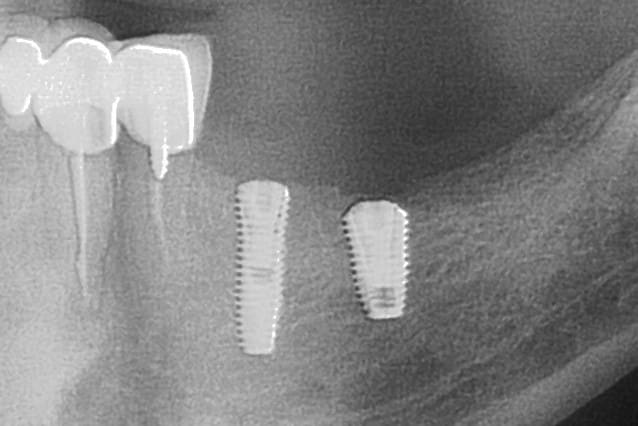

Superline x7zkzx - Eugenol

Oups

La toile résiduelle au niveau du col a l air qd même assez réduite sur le petit diamètre

Tu en penses quoi toi Pluton ???

Photo pluton1b h9n4ea - Eugenol

que la radio ne met pas vraiment en valeur cet implant...

le filetage externe est assez peu marqué en fait

mais tu as raison...c'est un petit diamètre...3.4mm pour le fût et 3.6mm au col

expansion pour ce cas...j'aurais aimé pouvoir y glisser un 4mm...mais l'os me disait "stop" pour le 3.6 en 12mm

l'implant postérieur est un 4.5/8

maintenant, un ID en 3.7mm ou un dentium en 3.6...on doit être assez proche...niveau finesse au col...